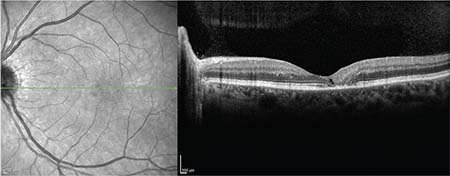

In addition, spectral domain optical coherence tomography (SD-OCT) may reveal hyporeflective cavities (ie, cavitations) involving the inner and/or outer retinal lamellae and ellipsoid zone attenuation (Figure 3). Although the entire perifovea may be involved, the findings are nearly always observed in at least the temporal edge of the fovea and may be asymmetric between the eyes.

| Figure 3. Horizontal spectral-domain optical coherence tomography of the left eye reveals a single cavitation through the middle layers of the retina with ablation of the ellipsoid zone just temporal to the central fovea. |